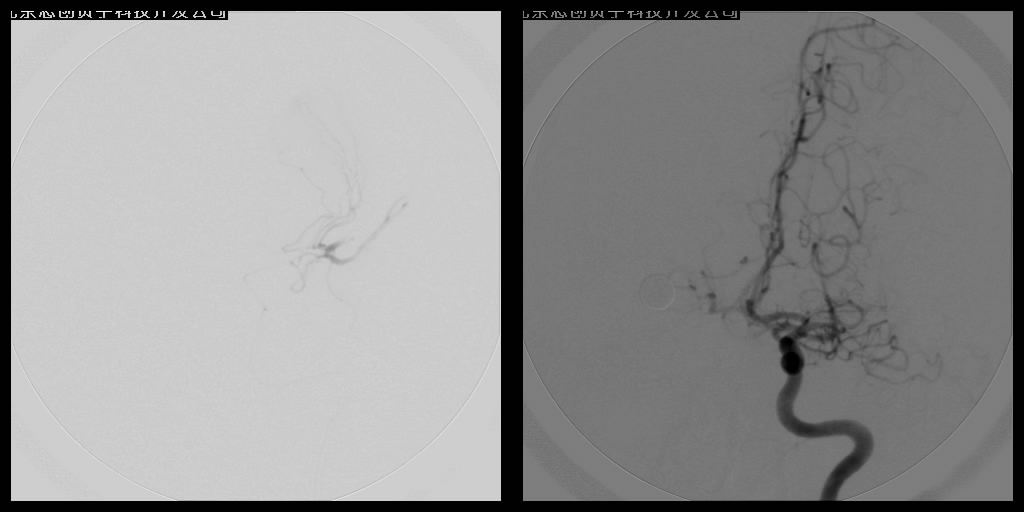

腦血管內(nèi)介入栓塞術(shù)

血管栓塞術(shù)主要應(yīng)用于出血性腦血管病的介入治療,如對顱內(nèi)動靜脈畸形的栓塞、硬腦膜動靜脈瘺栓塞、頸內(nèi)動脈海綿竇瘺的栓塞、頭頸部高血運腫瘤的栓塞等。